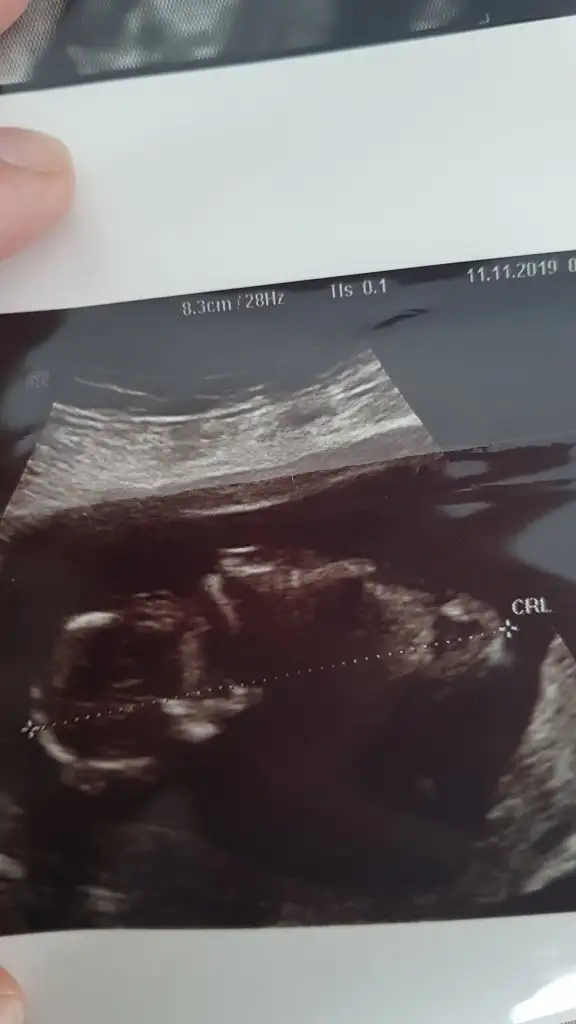

Bence erkekKuzular bide bana yorum yapın 10+5 im

Nub görünmüyor başka usg varmıKuzular bide bana yorum yapın 10+5 im

Doktorda erkege benzetti ama emin olamadımErkek olabilir :)

Evet cikinti var gibi dik cikinti sen genede ikisinede hazrlikli ol cnmDoktorda erkege benzetti ama emin olamadım

merhaba, ben de tahmin rica edebilir miyim? 11 hafta 2 günlük bebeğim :)